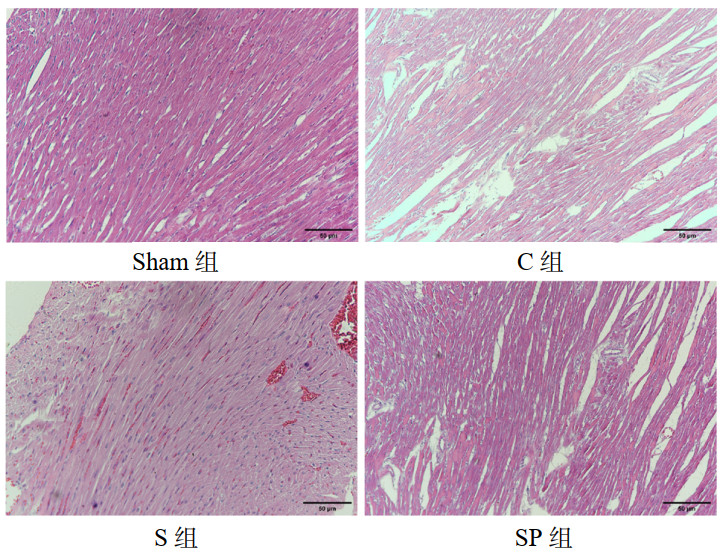

1.2.4 心肌组织病理检查大鼠心脏组织由4%多聚甲醛固定72 h,后经脱水、透明、石蜡包埋、切片、烤片、脱蜡、苏木素和伊红染色,观察心肌组织损伤程度及炎症细胞浸润情况。

sham组心肌细胞排列正常,无充血、水肿及渗出,心肌纤维排列紧密。C组心肌纤维断裂,心肌细胞有水肿,心肌纤维排列紊乱,心肌纤维横纹消失,间质血管扩张充血,间质大量炎症细胞浸润。与C组相比,S组心肌细胞水肿、坏死减轻,心肌细胞排列较前者规整,炎症浸润减少。SP组较S组心肌细胞水肿、坏死加重,心肌细胞排列较前者紊乱,心肌细胞空泡样变形增多,间质炎症细胞浸润增多。见图 2。

| 注:sham组为假手术组,C组为CLP模型组,S组为CLP+Sirt1激动剂组,SP组为CLP+Sirt1激动剂组+PGC-1α抑制剂组 图 2 四组心肌组织病理图(HE×200) Fig 2 Histopathologic picture of myocardial tissue in four groups (HE staining, ×200) |